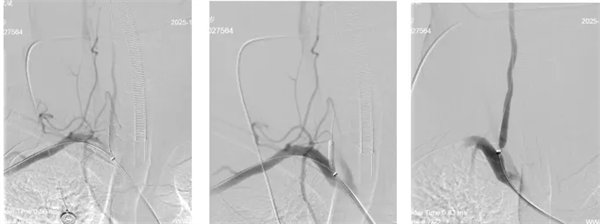

時間就是大腦!在與病人家屬充分溝通后,神經內三科介入團隊對患者進行了全麻下:顱內動脈取栓術+顱內動脈球囊擴張+椎動脈擴張+椎動脈支架植入術。

術中,介入團隊精準定位血管閉塞部位,通過微導絲“探路”聯合球囊擴張技術開通右側椎動脈開口,造影椎開口殘余狹窄60%?;讋用}血栓形成,基底動脈管腔狹窄55%,基底動脈尖堵塞,右側大腦后動脈及小腦上動脈未見顯影,左側大腦后動脈P3以遠閉塞。

席聰準確鎖定患者基底動脈處血栓,采用抽吸取栓技術快速開通血管,成功取出堵塞部位2cm的血栓。再次造影示:右側大腦后及雙側小腦上動脈再通,右側大腦后動脈P3段以遠閉塞,考慮慢性閉塞,推注替羅非班,血流明顯加快。隨后采用支架植入術開通右側椎動脈開口處,術中影像顯示:支架貼壁良好,無明顯殘余狹窄,顱內血管顯影良好。